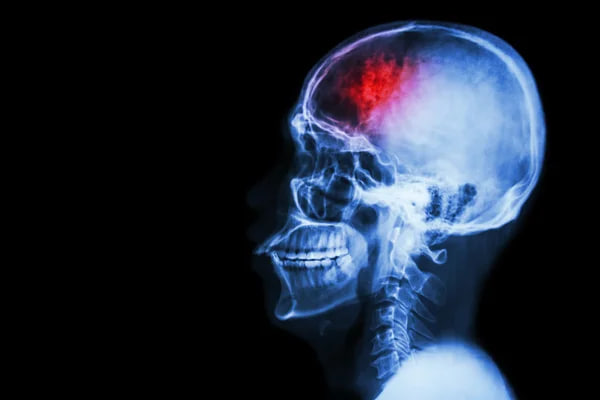

Фото: depositphotos

Американська асоціація інсульту (ASA) вперше за десять років оновила офіційні настанови щодо профілактики інсульту. За даними організації, до 80% випадків можна запобігти завдяки змінам у способі життя, контролю показників здоров’я та ранній діагностиці.